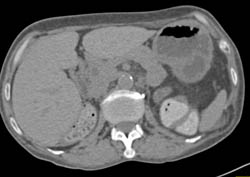

Renal Cell Carcinoma- See Full Sequence